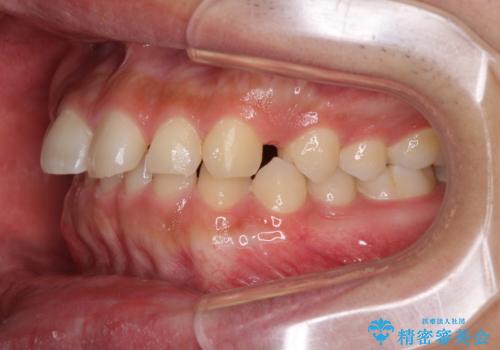

インビザラインによる、すきっ歯の改善

- 前歯がすきっ歯であることを気にして来院された患者様です。

下の前歯がほとんど隠れてしまうくらいの深い咬み合わせであったので、インビザラインを用いて、咬み合わせの高さを改善しながら隙間を閉じていくこととしました。

咬合力で上の前歯が前方に押し出されるようにして隙間ができていましたが、矯正治療により全て閉じることができました。

深い咬み合わせも多少改善され、隙間も閉じたことで、前方に出ていた前歯が引っ込んだため、口も閉じやすくなったとのことでした。